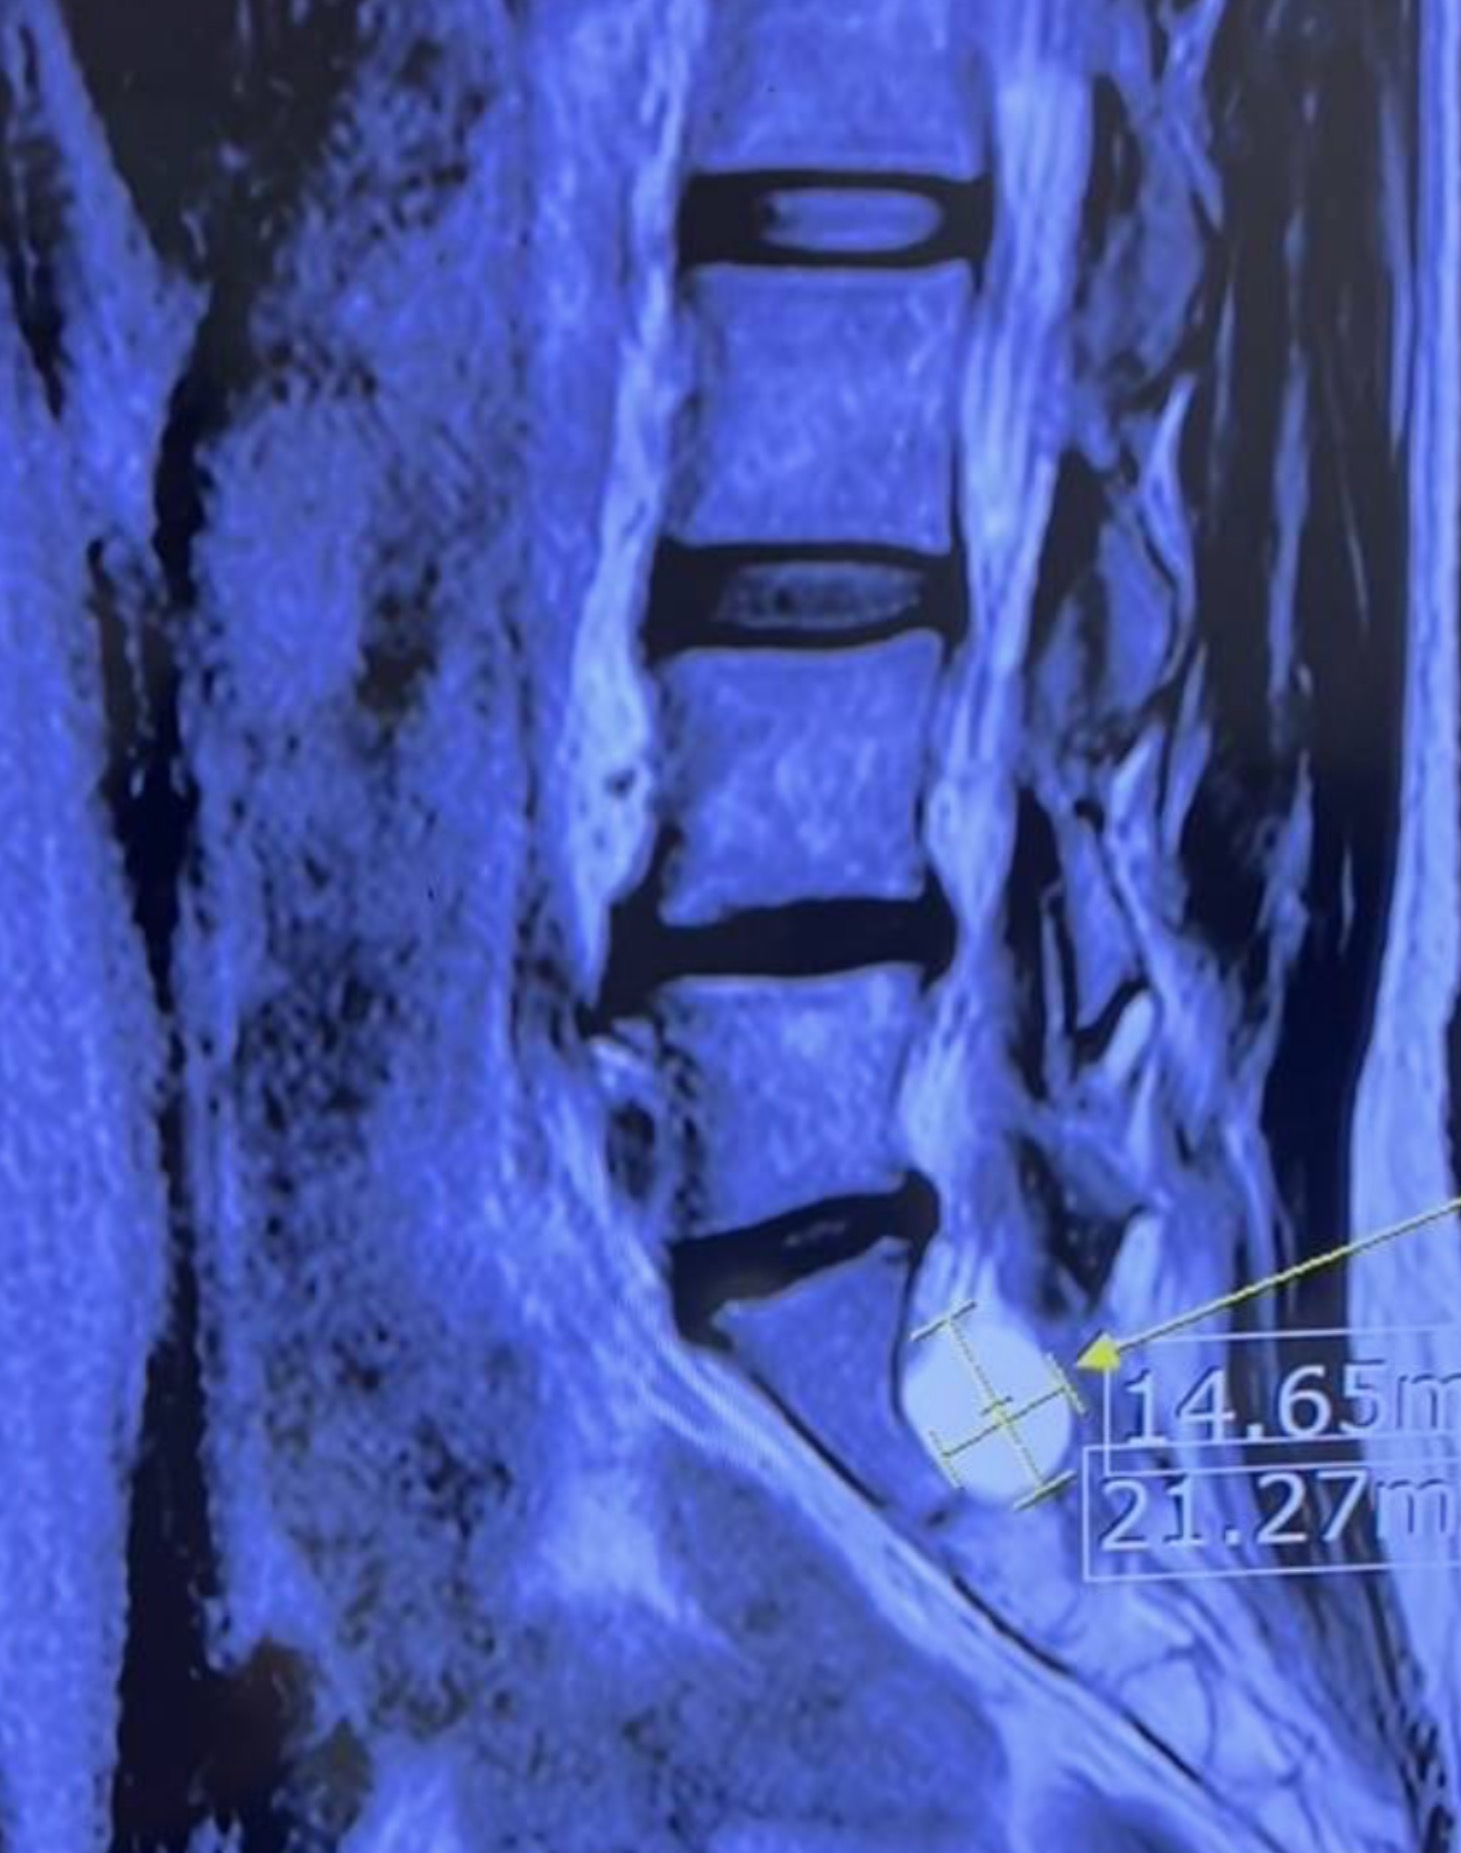

✔ 2) ดูขนาดถุงจาก MRI

- ถ้าถุง < 1 ซม. → โอกาสก่ออาการต่ำมาก

- ถุง > 2 ซม. → อาจมีแรงกดต่อเส้นประสาท